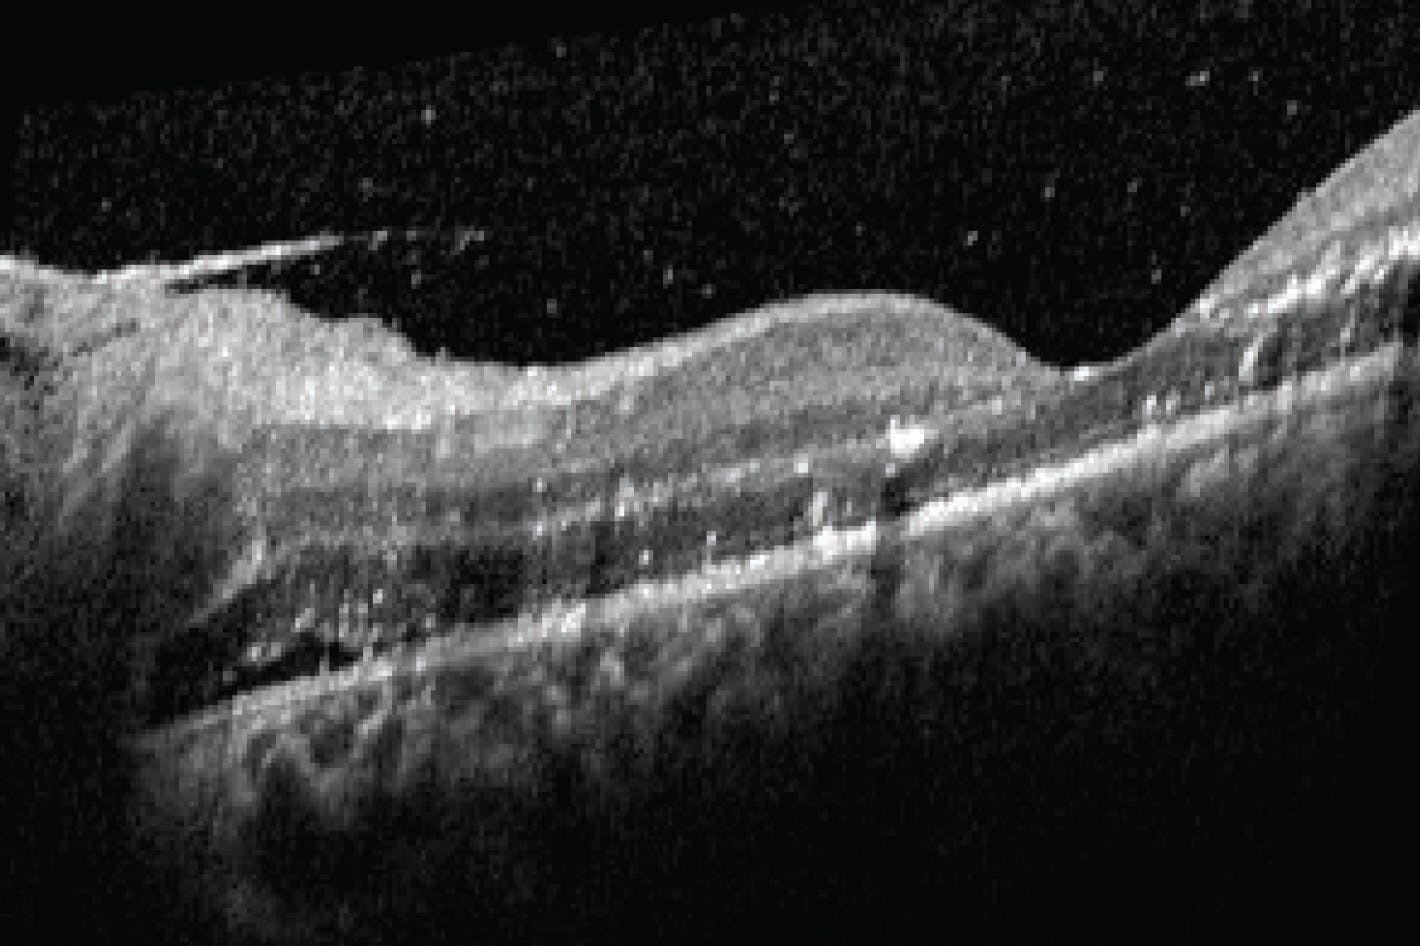

Posterior segment examination revealed disc edema that was greater in the left eye and macular edema with star pattern exudates OS and partial star pattern OD (Figure 1). OCT showed trace vitreous cell and subretinal fluid (Figure 2). Two multifocal white lesions of retinitis were noted OS nasally (Figure 3).

We discussed the likely diagnosis of CSD-NR given the clinical picture and history, and the decision was made to start oral doxycycline 100 mg twice daily for 4 weeks while awaiting serology results. At the 2-week follow-up visit, the patient’s vision had improved from 20/60 OD to 20/30 OD and from counting fingers OS to 20/60 OS with resolution of the relative afferent pupillary defect and subretinal fluid (Figure 4). He was seen again 2 weeks later after completing the course of doxycycline, at which point his nerve edema had resolved, although exudate deposits remained in the left fovea. His VA was 20/25 OD and 20/50 OS, likely due to remaining exudates. He was scheduled to return in 1 month but was lost to follow up.